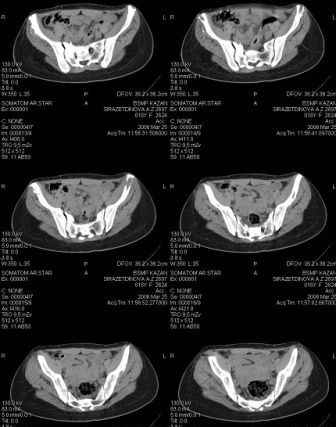

Уважаемые коллеги! Девушка 18л сросшиеся переломы лонных, седалищных костей с обеих сторон, перелом крестца справа,перелом костей голени справа (зио), 3 мес после травмы, АВФ снят с таза. Патологической подвижности нет. Стоит самостоятельно, ходит с костылями, поскольку 3 месяца практически не ходила. Беспокоит выступание лонной кости в области лобка, хотя объективно грубого косметического дефекта нет. На кт разворот лонной кости в сагиттальную плоскость. Вопрос: стоит ли добиватьсяполной репозиции или же достаточно произвести остеотомию верхушки выступающего отломка?

Предварительный диагноз- посттравматическая вертикальная нестабильная деформация таза II степени, неправильно срастающийся перелом боковой

массы крестца справа, правой лонной и седалищной костей, застарелый разрыв лонного сочленения.

Для уточнения диагноза ниеобходимы обзорные рентгенограммы таза (прямая и inlet), Кт срезы на уровне переломов для определения степени сращения и решения вопроса о методе оперативного восстановления анатомии (делать ли остеотомию, низводить ли задние отделы), ни о какой "остеотомии выступающих отломков" тем более у девочки 18 лет речи быть не может.

Предоставляю срезы. Если пациентку функционально ничего не беспокоит, стоит ли навязывать ей лечение.